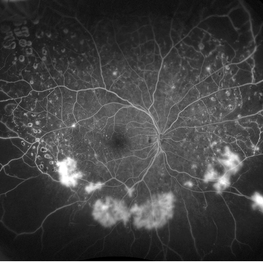

Retinal Ischemia

Jul 11 2018 by Sarah Oelrich

Retinal Ischemia, PDR

Photographer: Sarah Oelrich CRA, Southeastern Retina Associates, Knoxville TN

Imaging device: Optos 200tx

Condition/keywords: ischemia